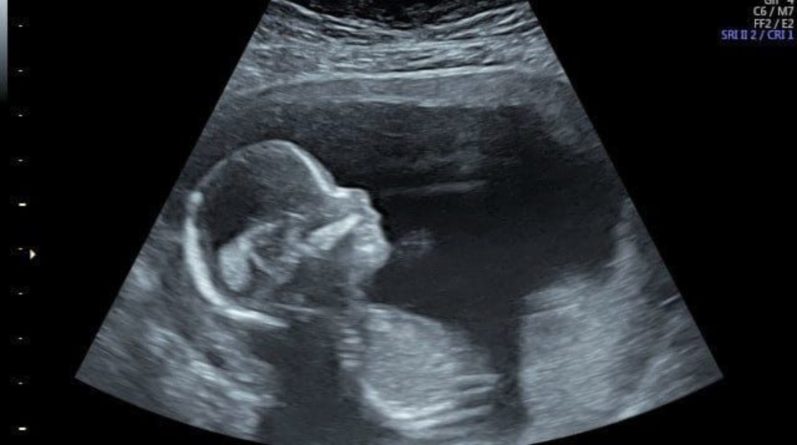

Хирурги выполнили новаторскую операцию на 24 неделе беременности после того, как УЗИ показало, что у ребенка расщепление позвоночника. Этот порок развития может привести к затруднениям при ходьбе и даже параличу, поскольку спинной мозг не развился полностью во время беременности.

Хирурги из Университетского колледжа Лондона и Great Ormond Street Hospital вместе с бельгийскими коллегами смогли восстановить спинной мозг, и теперь есть надежда, что ребенок родится здоровым в апреле.